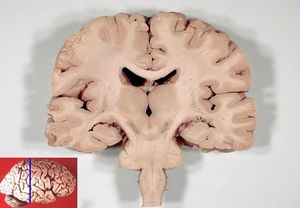

신경조직은 신경세포체와 축삭의 분포에 따라 회색질과 백색질로 구분된다.

중추신경계에서 신경세포체가 모여 있는 부분은 비교적 짙게 보여 회색질이라고 부르고, 축삭이 모여 있는 부분은 미엘린 때문에 희게 보이므로 백색질이라고 부른다. 회색질에는 신경세포체와 가지돌기가 있으므로 시냅스도 대부분 이곳에서 이루어진다. 축삭, 가지돌기 및 신경아교세포 돌기들이 어지럽게 얽혀 신경그물(neuropil)을 이룬다. 백색질에는 축삭, 신경아교세포, 혈관이 있으며 신경세포체는 존재하지 않는다. 백색질의 축삭 가운데 출발 지점과 도착 지점이 서로 비슷해 구조적, 기능적으로 밀접하게 연관되어 있는 것들을 묶어 신경로라고 일컫는다.[22]

회색질과 백색질의 배열 양상은 부위에 따라 다르게 나타난다. 척수에서는 회색질이 안쪽, 백색질이 바깥쪽에 위치한다. 대뇌와 소뇌에서도 중심부에 바닥핵(기저핵)이라는 회색질 덩어리들이 존재하고 백색질이 그 주변을 둘러싸고 있지만, 척수와 달리 가장 표면 부위에 추가적으로 회색질 층이 있어서 대뇌겉질 및 소뇌겉질을 형성한다. 뇌줄기에서는 회색질과 백색질을 구분하기 어렵다.[22]

3. 1. 회색질과 백색질

회색질은 신경세포체, 가지돌기, 무수축삭, 신경아교세포 등이 모여 있는 영역으로, 주로 정보 처리를 담당한다. 백색질은 유수축삭, 신경아교세포 등이 모여 있는 영역으로, 신경세포 간의 정보 전달 통로 역할을 한다. 뇌와 척수에서 회색질과 백색질의 배열 양상이 다르다.[22]척수에서는 회색질이 안쪽에, 백색질이 바깥쪽에 위치한다. 대뇌와 소뇌에서도 중심부에 바닥핵(기저핵)이라는 회색질 덩어리들이 존재하고 백색질이 그 주변을 둘러싸고 있지만, 척수와 달리 가장 표면 부위에 추가적으로 회색질 층이 있어서 대뇌겉질 및 소뇌겉질을 형성한다. 뇌줄기에서는 회색질과 백색질을 구분하기 어렵다.[22]